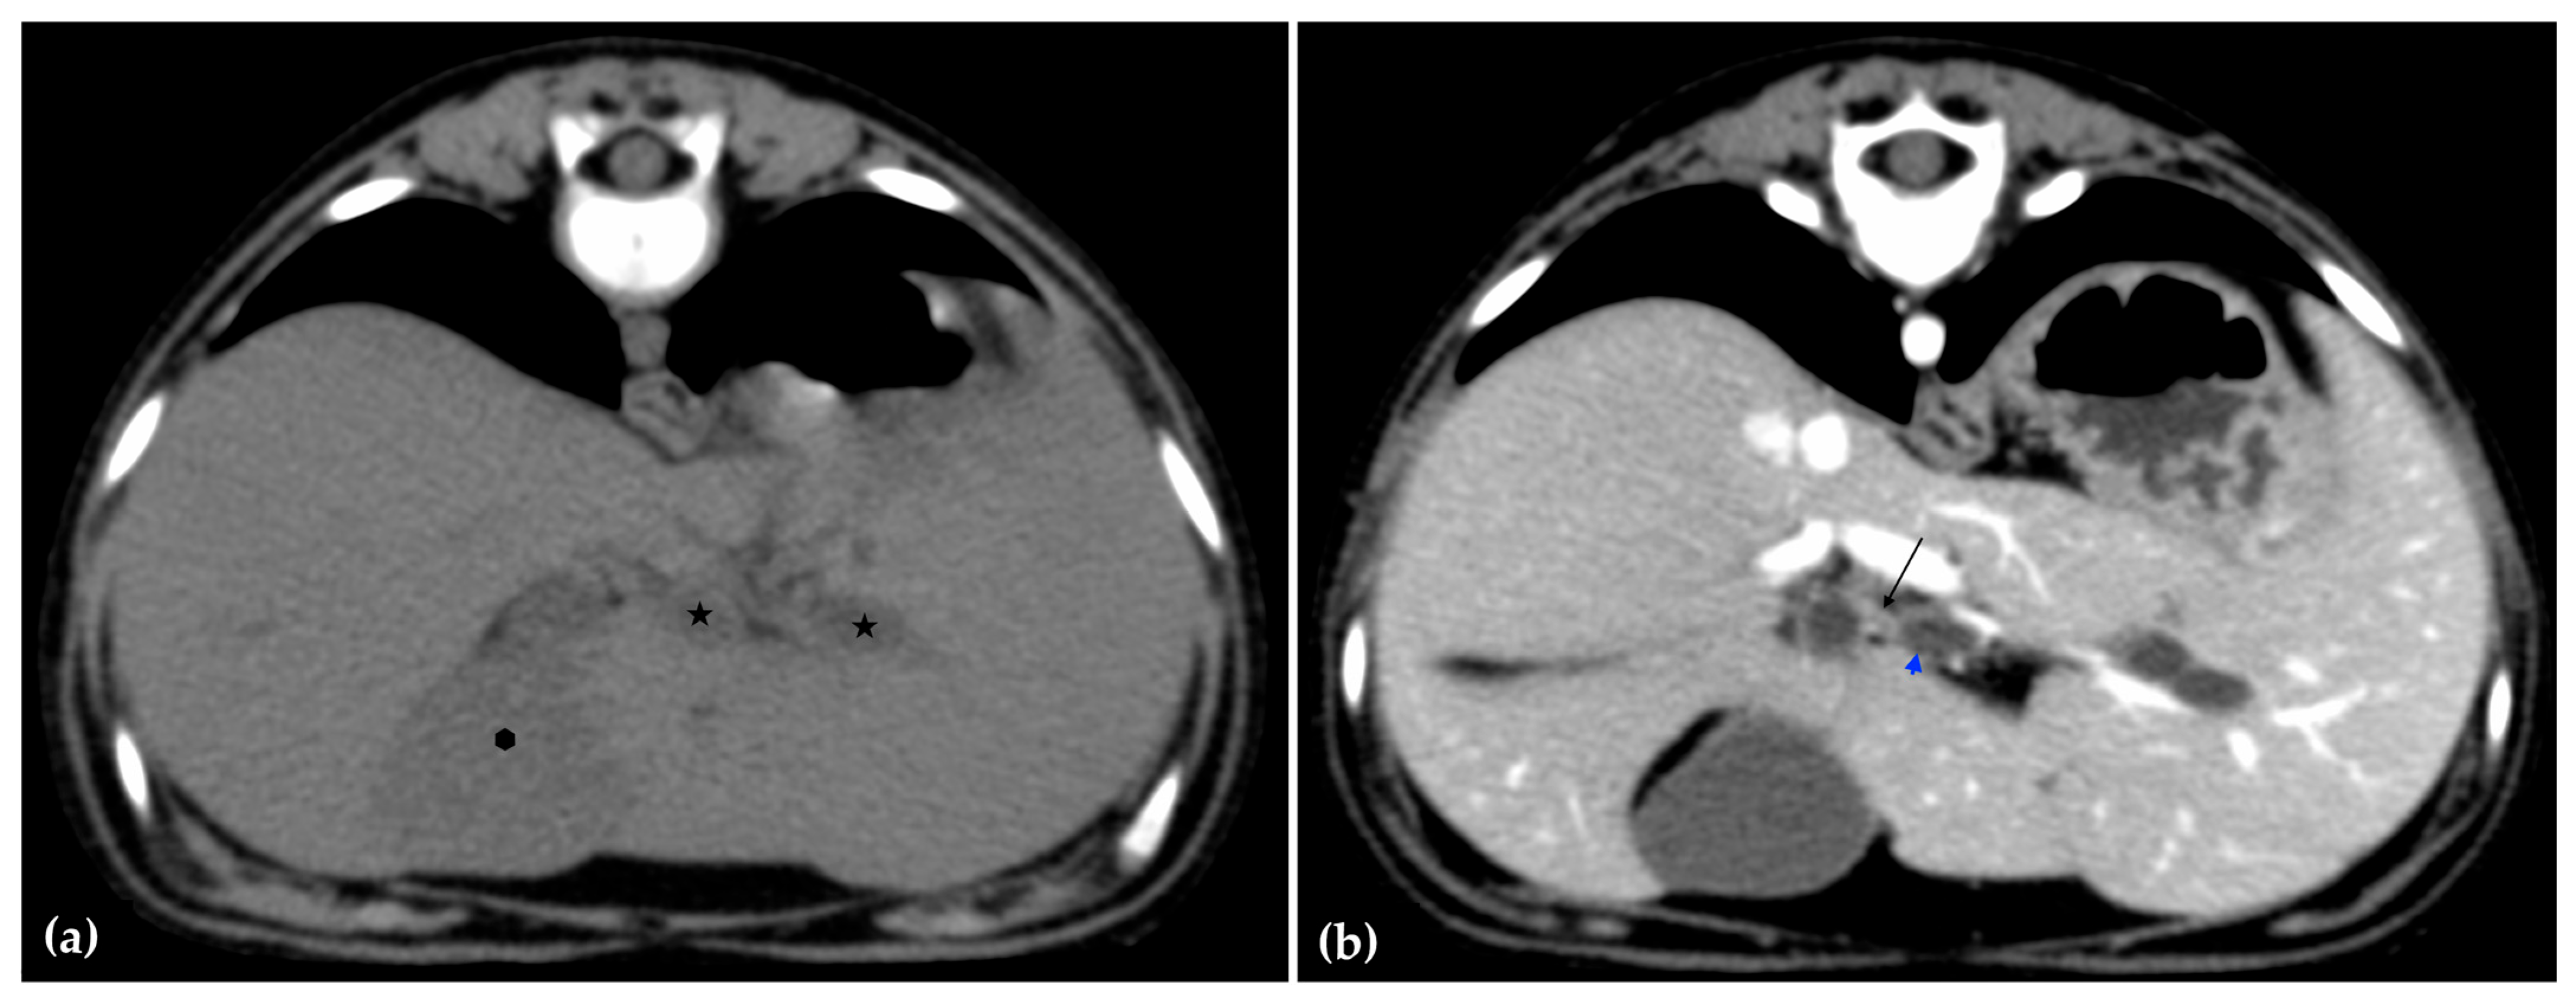

The patient was positioned in sternal recumbency. Helical scans of the abdomen using a multidetector CT were obtained with pre-contrast, post-contrast arterial, portal, and delayed images, all in a soft tissue reconstruction kernel (acquisition parameters: Slice thickness 0.9 mm, pitch 0.8, tube rotation time 0.5 s, 412 mA, 120 kVp, 512 × 512 matrix; Philips Brilliance-40, Philips International B.V., Amsterdam, Netherlands). Prior to contrast administration, the gallbladder was noted to be filled with predominantly mildly hyperattenuating (av. 25 HU) fluid. Dilation of the distal left intrahepatic biliary ducts were again seen (Figure 3a). Following intravenous contrast administration (Optiray 350™ Ioversol, Mallinckrodt Inc., Hazelwood, MO, USA; or Omnipaque 350™ Iohexol, GE Healthcare Inc., Marlborough, MA, USA), multifocal dilation and tortuous narrowing of the CBD was seen and best appreciated in the portal phase. There was increased conspicuity of the walls, both in contrast enhancement and wall thickness (Figure 3b and Figure 4a,b). No intraluminal debris or extraluminal structures to explain the multifocal dilation was appreciated.

Figure 3.

Computed tomographic (CT) pre-contrast image of the liver at the level of the gallbladder (hexagon). There is distention of the left distal intrahepatic biliary ducts (stars). The right of the patient is on the left (a). Computed tomographic (CT) post-contrast image (portal phase) at the level of the cystic duct (black arrow). Immediate dilation of the common bile duct (blue arrowhead) (b).